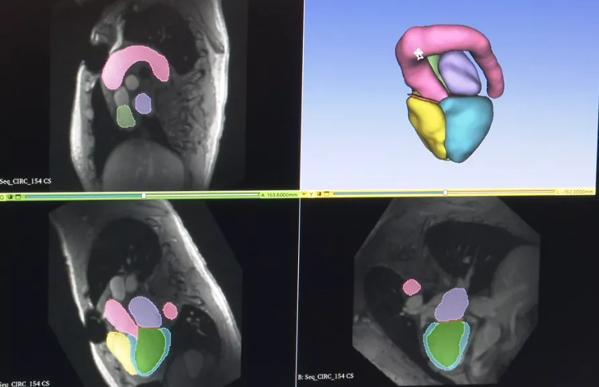

“Some examples include being able to use AI to help process data for certain studies like echocardiograms, or CT scans, or MRI and free up some of the more basic data processing tasks to AI,” he explained.